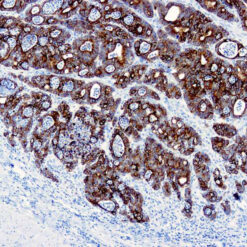

Prostate Specific Antigen, PSA

This product is intended for qualitative immunohistochemistry with normal and neoplastic formalin-fixed, paraffin-embedded tissue sections, to be viewed by light microscopy. Clinical interpretation of staining results should be accompanied by histological studies with proper controls. Patients’ clinical histories and other relevant diagnostic tests should be utilized by a qualified person(s) when evaluating and interpreting results.

| Immunogen | Prostate specific antigen isolated from human seminal plasma. |

| Positive Control Tissue | Prostate carcinoma |